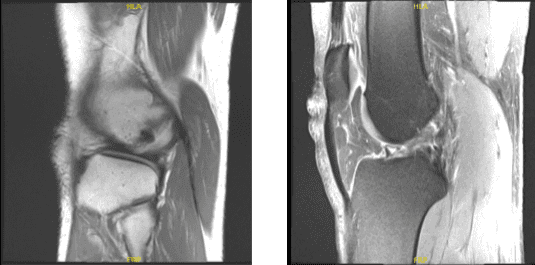

MRI right knee non-contrast

The patient is a 38-year-old guy who came into the office complaining of discomfort and instability in his right knee. He added that he had previously seen a doctor who diagnosed him with an ACL tear. A knee MRI was done which confirmed the absence of ACL. Physical examination was positive for ACL deficiency.